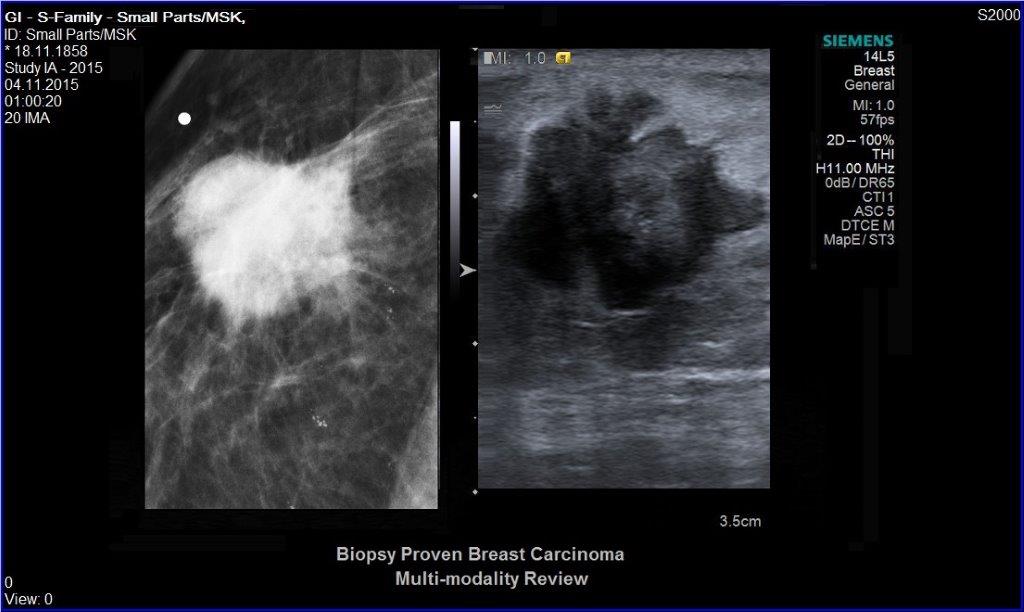

• Ultraschalluntersuchung der Brust